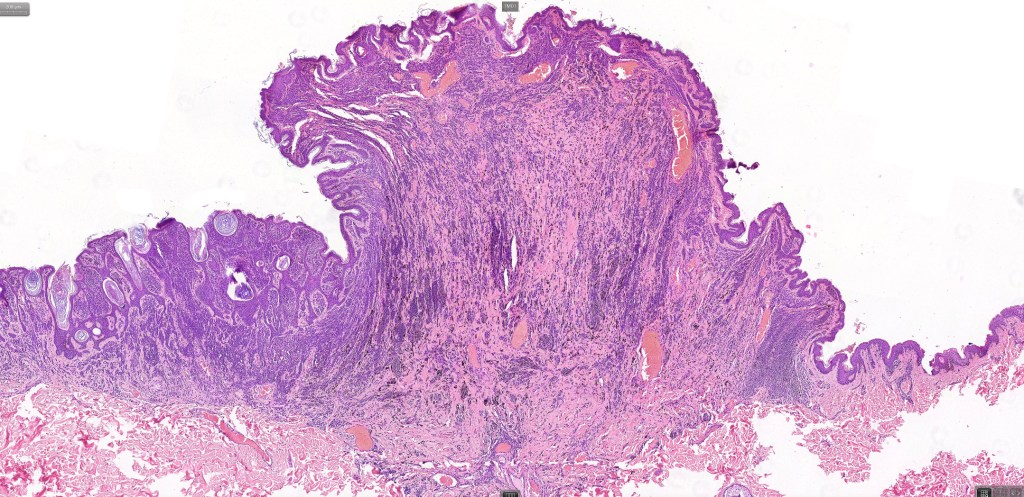

This is uncommon and presents clinically with a history of recent change in color of a common or less often congenital nevus causing concern for melanoma by the clinician. Some, but not all are probably deep penetrating and combined nevus variants. Others may represent follicular type-A cell nests. It is characterized by the presence of deep nest(s) of type -A nevus cells surrounded by & with overlying type-B nevus cells.